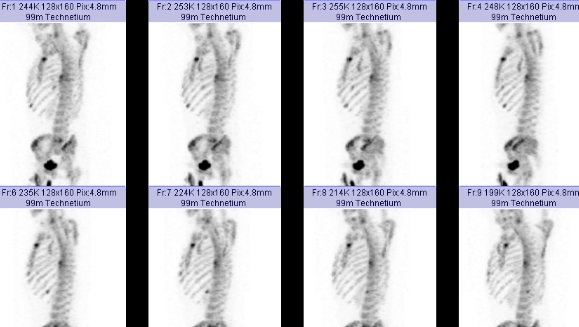

全身骨シンチグラフィ 乳癌 肺癌 前立腺癌等の骨転移病巣の検出

主な核医学検査 骨 骨シンチグラフィ 核医学検査のご案内 医療関係者

骨シンチグラフィーとは 佐賀大学病院放射線科アンオフィシャル

全身骨シンチグラフィ 乳癌 肺癌 前立腺癌等の骨転移病巣の検出

骨シンチグラフィによる骨転移の診断 Bone Scan Ct Mri画像診断